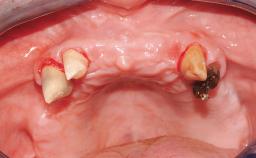

Immediate Loading of Six Implants in the Mandible and Six Implants in the Maxilla and Final Restoration with Full-Arch CAD/CAM Metal Framework FDPs Involving Digital Planning and Guided Surgery

Case Type Edentulous Maxilla

Jaw Maxilla and Mandible

Defining Characteristics Fully edentulous upper jaw to be rehabilitated with four or more implants